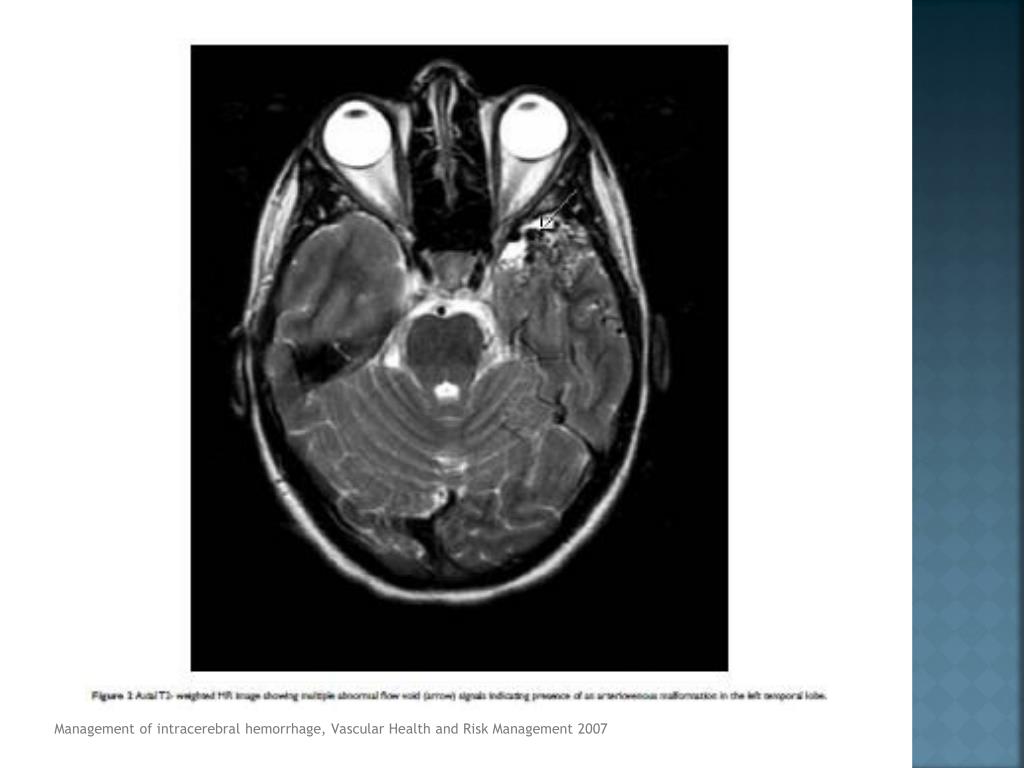

18. Tomografía axial computarizada (TAC) método dx. de elección (Clase 1A) • CT Angiography o TAC resalte de contraste • Expansión de hematoma (Clase IIB) • RMN (Clase 1A) • Hemorragia hiperaguda menor a 6 horas • Causa subyacente • Angiografía • Ptes. menores de 45 a • No riesgo de HIC primaria o hipertensiva • HSA • Estructuras vasculares prominentes • Hemorragia perisilviana o interhemisferica Management of intracerebralhemorrhage, Vascular Health and Risk Management 2007, Guidelinesforthe Management of SpontaneousIntracerebralHemorrhage, AHA/ASA 2010

19. Management of intracerebralhemorrhage, Vascular Health and Risk Management 2007

20. Management of intracerebralhemorrhage, Vascular Health and Risk Management 2007